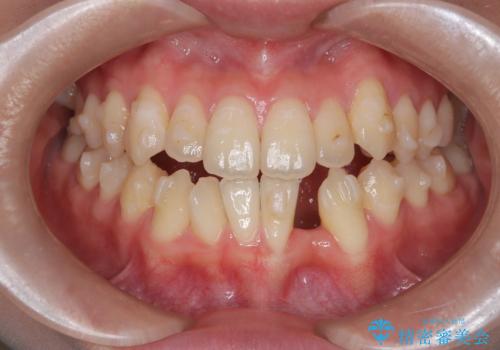

前歯の突出を防ぎながらガタつきを解消。上下左右4番抜歯による審美ワイヤー矯正

担当医 河口智英